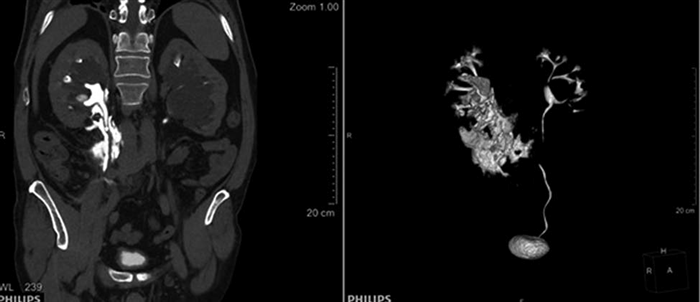

При ультразвуковом исследовании определено скопление жидкости в правом периренальном пространстве, выявлена гидронефротическая деформация правой почки. Левая почка обычных размеров с единичными простыми кистами. Для уточнения диагноза было проведено рентгенологическое обследование, по результатам которого диагностированы МКБ, конкремент правого мочеточника в верхней трети, дефект стенки лоханки правой почки в области пиелоуретерального сегмента с затеком контрастированной мочи в паранефральную, парауретеральную и забрюшинную клетчатку (рис. 1 а, б).

Рис. 1. Компьютерная томография:

а — конкремент верхней трети правого мочеточника, уринома справа; б — разрыв ЧЛС правой почки, уринома справа.

В условиях общей анестезии было проведено дренирование правой почки путем чрезкожной перкутанной нефростомии и стентирования правой почки (рис. 2). Уринома дренирована пункционно. В послеоперационном периоде отмечались уменьшение выраженности болевого синдрома, значительное улучшение общего состояния и лабораторных показателей (креатинин — 99,54 мкмоль/л; мочевина — 7,02 ммоль/л; С-реактивный белок — 37,84). Контрольная компьютерная томография показала отсутствие экстравазации контрастного вещества из почечной лоханки. Конкремент из верхней трети правого мочеточника смещен краниально и визуализируется в верхней группе чашечек правой почки.

Рис. 2. Рентгенограмма. Дренированная правая почка